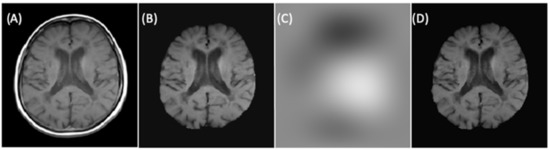

Figure 5 illustrates the skull-stripping process using the U-Net architecture for brain extraction described in step five.

Figure 5.

(A) Slices from original T1-w image. (B) Brain mask through skull-stripping using CNN. (C) Brain extraction in T1-w. (D) Brain extraction in FLAIR image.